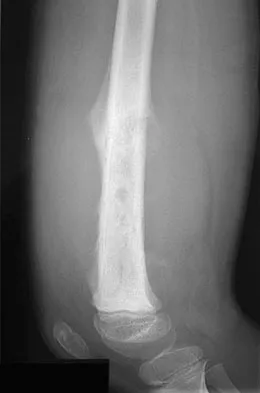

Question 644High Yield

A 24-year-old woman was struck by a mini van in a parking lot and sustained a closed segmental tibia fracture that was treated with an intramedullary nail the following morning. Follow-up examinations reveal a slowly progressive clawing of all five toes, a progressive equinocavovarus contracture, and the patient is unable to perform a single heel rise on the affected limb. At 1 year after surgery, the patient now has a 10-degree equinus contracture that is not relieved with knee flexion. Treatment should now consist of

Explanation

This is an example of a missed deep posterior compartment syndrome that typically presents 6 months after the injury with progressive clawing due to necrosis, scarring, and contracture of the posterior tibial tendon, flexor digitorum longus, and flexor hallucis longus. Treatment consists of debridement of necrotic muscle and scar tissue with corresponding tendon excision. After debridement and posterior capsule release, if the equinus is relieved with knee flexion, a gastrocnemius slide may be performed. Otherwise, the lengthening should be at the level of the Achilles tendon. Bracing will not address the claw toes. Hansen ST Jr: Functional Reconstruction of the Foot and Ankle. Philadelphia, PA, Lippincott Williams & Wilkins, 2000, pp 212-213. Manoli A II, Smith DG, Hansen ST Jr: Scarred muscle excision for the treatment of established ischemic contracture of the lower extremity. Clin Orthop Relat Res 1993;292:309-314.